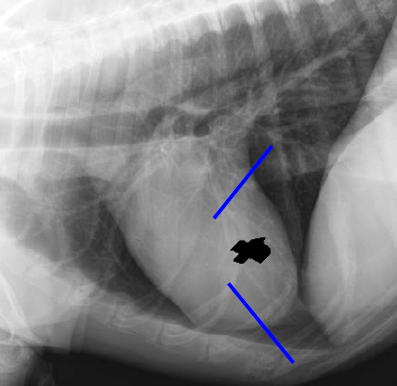

Lateral

2 to 5 left ventricle

5 to 9

Right ventricle

9 to 11